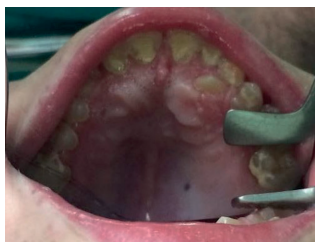

No es frecuente que estos pacientes presenten alteraciones a nivel dentario y gingival como en otros tipos de MPS, pero sí se ha observado una mayor incidencia de bruxismo. Además, pueden presentar dientes supernumerarios con la consiguiente maloclusión que, debido al deterioro del sistema nervioso central desde edades muy tempranas, no puede llevarse a cabo el control por el ortodoncista. En los casos en que, debido a inclusiones dentarias o dientes supernumerarios que provocan patología y se requiere su tratamiento quirúrgico, éste deberá llevarse a cabo bajo sedación25-27 (Figuras 6, 7 y 8).

Cuando comienzan el recambio dentario, se debe mantener continuas revisiones odontológicas, puesto que en estos casos existen problemas para la exfoliación de los dientes deciduos. Se pueden encontrar dientes supernumerarios e inclusiones dentarias, que serán extraídos por un especialista en quirófano bajo sedación profunda, debido a la alteración cognoscitiva importante que suelen presentar y/o hiperactividad en fases intermitentes39 (Figuras 9, 10 y 11).